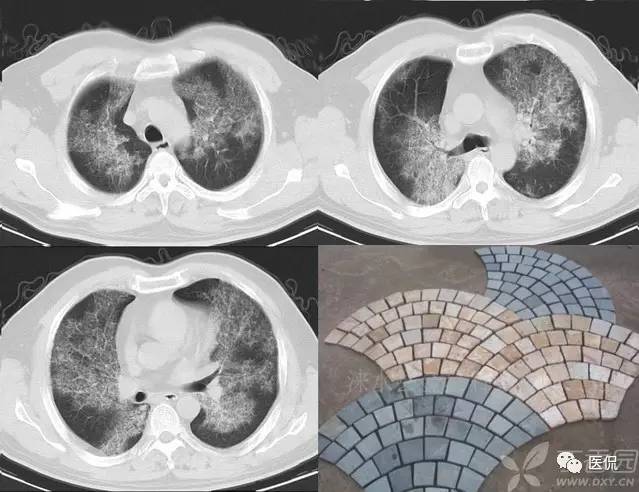

碎石路征

碎石路征或称铺路石征,是胸部CT上的一种影像学征象,主要表现为在弥漫性或散在分布的毛玻璃样浸润影中,有小叶间隔增厚、小叶内线状影重叠存在。碎石路征最初在肺泡蛋白沉积症(PAP)的病例中发现,并认为是PAP特征性的胸部CT表现;但实际上,感染性疾病、肿瘤、特发性肺弥漫性疾病(DPLD)、吸人性病变等都也可以出现。

1)卡氏肺囊虫肺炎(PCP):PCP是由卡氏肺抱子虫引起的肺部机会性感染,多发生于免疫功能严重受损者,是艾滋病(AIDS)患者发生机会性感染和致死的主要原因。PCP的主要症状包括干咳、呼吸困难和低热。典型的胸部X光片改变是双侧、沿肺门周围分布的网状影和境界不清的毛玻璃影;这种改变在CT上则表现为典型的碎石路征。引起碎石路征的病理学基础是:毛玻璃影由肺泡内泡沫样渗出,伴肺泡壁增厚引起;小叶间隔内水肿和慢性炎症细胞浸润致小叶间隔增厚、小叶内线状影。

2)严重急性呼吸综合征(SARS):SARS是一种起病急、病情发展迅速、人群普遍易感、死亡率较高的新的传染性肺部疾病。病理改变主要表现为弥漫性肺泡损伤(DAD),即肺充血、出血、水肿、透明膜形成、肺泡上皮细胞增生,部分肺泡腔内可见到脱屑的肺泡细胞、巨噬细胞和多核巨细胞,伴间质中炎症细胞浸润。主要临床表现是:发热(体温>38℃)、咳嗽、气短、呼吸困难等。胸部X光片可见大片状或斑片状分布实变影。部分SARS患者在起病2周内胸部CT上可发现碎石路征;在疾病的不同时期CT的表现形式有所不同,当早期以分散的、局灶性毛玻璃影为主要表现时,可见碎石路征,继而可以出现实变、间质增厚、胸膜反应和疤痕策划。

1)PAP是一种罕见病。各个年龄均可发病,以20~50岁的成年人多见。干咳、呼吸困难是其最常见的临床症状,而胸膜性胸痛、乏力、低热等则较少见。其胸部X光片表现是双侧对称性的肺泡实变或毛玻璃影,主要分布于肺门及肺门周围而类似肺水肿。CT的典型表现包括:①毛玻璃影及实变影与小叶间隔增厚交织形成碎石路征样改变;②在肺泡实变与正常的肺实质之间出现很明显的分界线,形成“地图样”分布。PAP碎石路征的策划学基础是:毛玻璃影及实变影与肺泡内充满PAS染色阳性、富含脂质的蛋白样物质有关;小叶间隔增厚影与肺泡壁因纤维策划增生或II型肺泡上皮细胞增生及淋巴细胞浸润有关。依据碎石路征和“地图样”分布,结合患者临床与影像学表现不平行的特点,是诊断PAP的诊断的不要依据。

典型的肺泡蛋白沉积症: